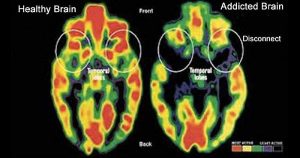

How Trauma Affects the Brain

Today it’s much easier to see how trauma and addiction go hand in hand. Due to advances in neuroscience we now know:

- The amygdala (your brain’s threat detection center) can become overactive, engaging in a constant program of looking for, seeing and assessing threat. This will cause you to feel intensely anxious, vulnerable and fearful.

- The hippocampus (your brain’s center for processing memories) can become underactive. Rather than consolidating and then placing memories in the outer layer of the brain for long-term storage, memories get hung up in a present-day loop. The result: You will experience and re-experience intrusive, disturbing and uncomfortable recollections.

- The cortex (your brain’s center for executive control) becomes interrupted by survival-oriented instincts from deep inside your inner brain. These instincts overrule logical thinking, diminish cognitive processing and decrease your ability to inhibit behavior. Even when you try to refrain from addictive behavior you will experience an unstoppable urge to engage in it.

Trauma affects the way our brains function.